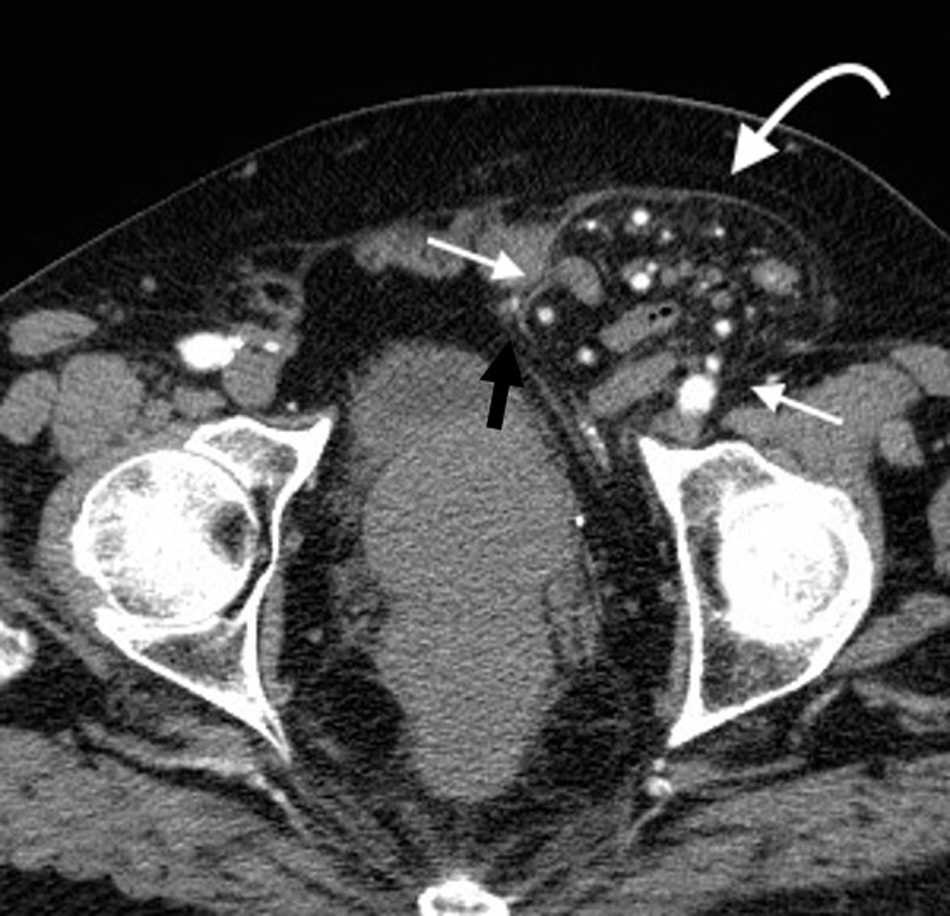

La hernia inguinal indirecta atraviesa el anillo inguinal interno, recorre el conducto y emerge a trav??s del anillo externo, sobresaliendo superior y externamente a los vasos epig??stricos inferiores. Puede extenderse por el conducto esperm??tico o el ligamento redondo hacia el escroto o los labios mayores, respectivamente. Es posible ver el cuello del saco herniario en el anillo inguinal profundo1 (fig. 1). Un hallazgo que ayuda a su caracterizaci??n es el signo del gancho. Este debe su nombre a la forma c??ncava que adopta la arteria epig??strica inferior en el plano axial en su curso proximal, al ser comprimida por una hernia indirecta6.

En lo que respecta a la directa, esta se ubica por encima del ligamento inguinal y medial a los vasos epig??stricos inferiores, y en general es adquirida. Su incidencia aumenta con la edad por el debilitamiento de la fascia transversal en el tri??ngulo Hesselbach1. Suele ser m??s frecuente en hombres y est?? menos asociada a la estrangulaci??n de las asas, posiblemente porque en general no atraviesa todo el curso del canal4 (fig. 2). El contenido del canal inguinal es comprimido lateralmente, mientras que su grasa se ubica como una luna creciente, produciendo el signo de la semiluna creciente (un hallazgo que ayuda a la caracterizaci??n de estas hernias)7.